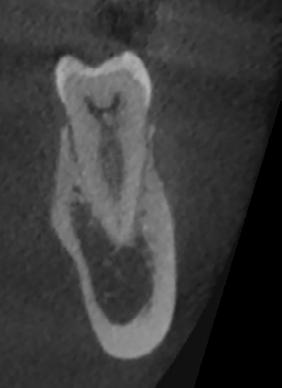

El desarrollo de técnicas avanzadas de radiodiagnóstico como el examen de tomografía computarizada de haz cónico (CBCT) ha permitido un mejor diagnóstico y planificación de la microcirugía endodóntica y la localización del ápice radicular, mejorando la tasa de éxito de la cirugía endodóntica.13

El desarrollo de técnicas avanzadas de radiodiagnóstico como el examen de tomografía computarizada de haz cónico (CBCT) ha permitido un mejor diagnóstico y programación de la microcirugía endodóntica y la localización del ápice radicular, mejorando la tasa de éxito de la cirugía endodóntica. Además, el desarrollo de la técnica de navegación estática asistida por computadora (SN) permite una guía de perforación durante los procedimientos de microcirugía endodóntica, mejorando la precisión de la ubicación del ápice radicular y permitiendo una microcirugía endodóntica precisa y segura, especialmente en la región posterior.12